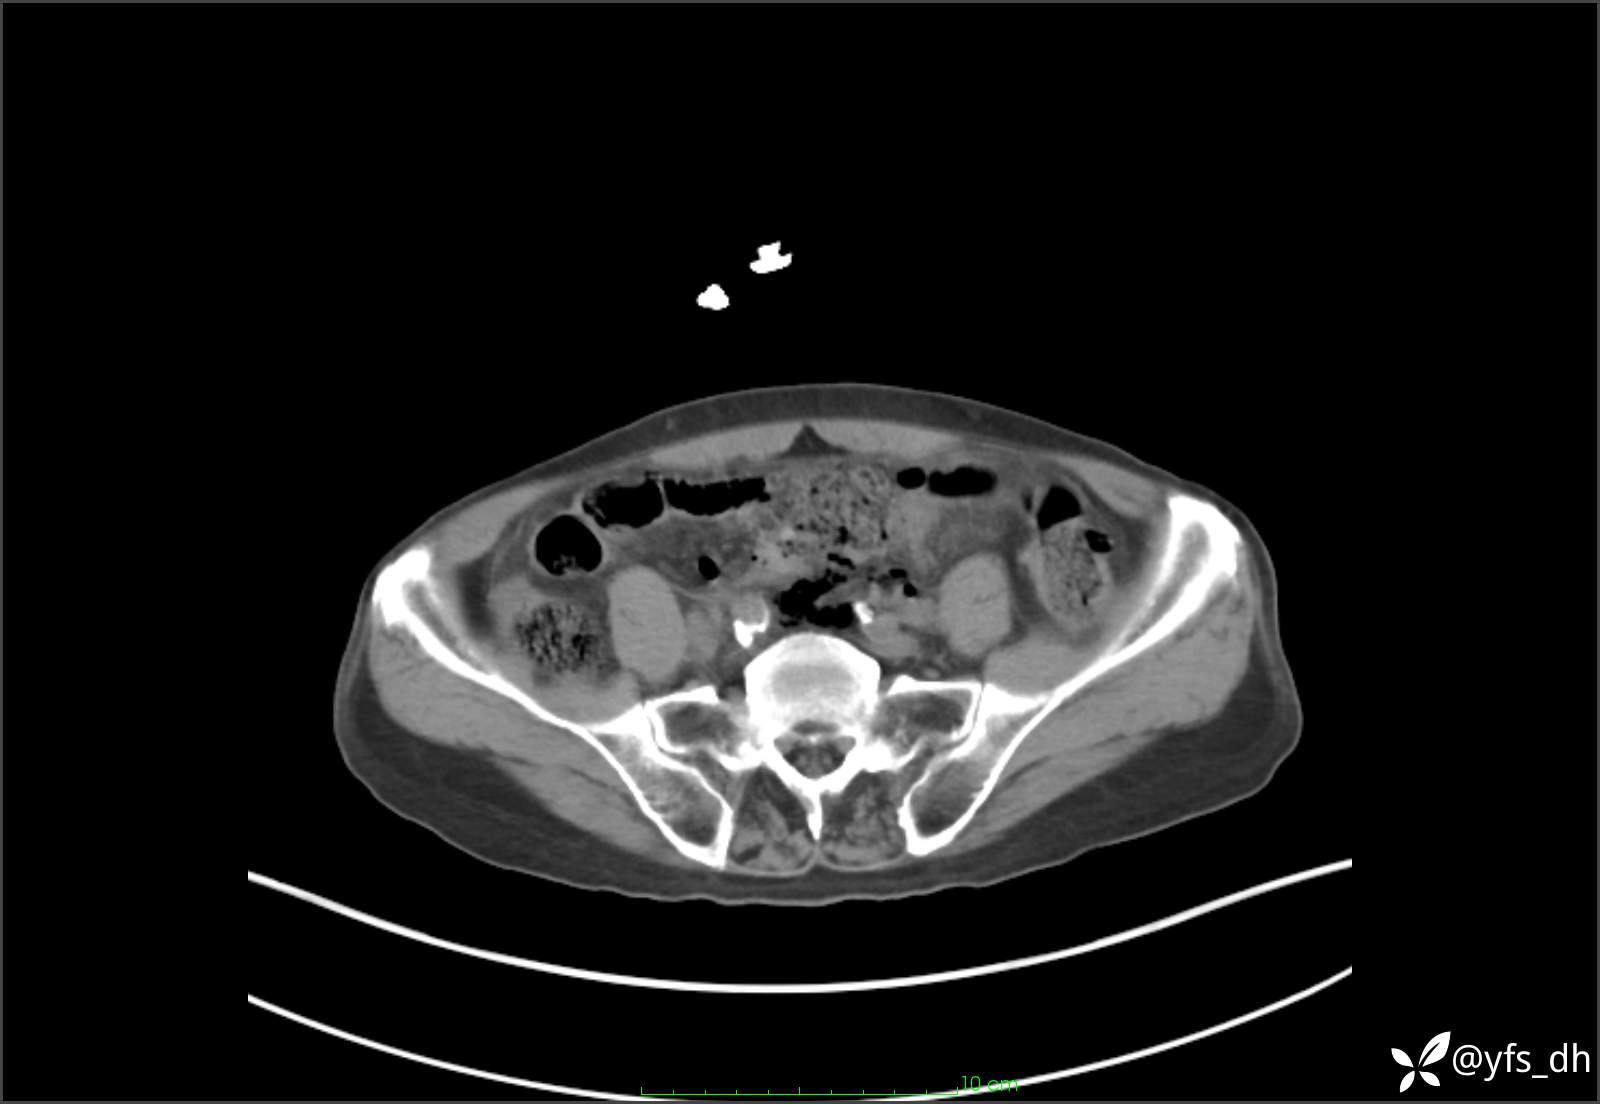

1.简要病史:患者4天前突发上腹部疼痛不适,但可以忍受。3小时前饭后突然加重,不能忍受后就诊。

2.简要手术记录:术中见腹盆腔大量肠液及粪便,乙状结肠中下段见一约3cm的破口。